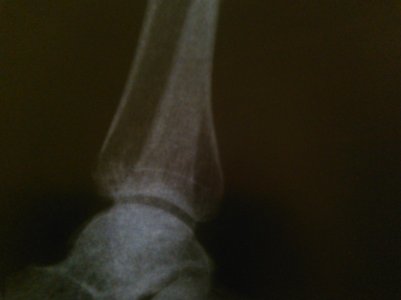

Отдельно прилагаются фото МРТ, КТ, рентгенография.